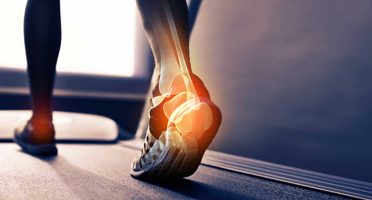

Lesiones del deporte

• Lesiones

- Fracturas

- Lesiones musculares

- Lesiones articulares

- Lesiones meniscales, etc.